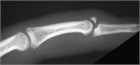

伸筋腱剝離損傷(Mallet finger)は,一般的に指先への直接打撃の結果として発症する.フットボールやバスケットボール等の球技で発症しやすい.指は遠位指節間関節(distal inter phalangeal:DIP関節)で屈曲した状態となり能動的に伸展させることができない.「伸筋腱断裂」と「伸筋腱付着部の剝離骨折」のどちらでも起こるため鑑別のためにX線検査が必要である.初期治療は保存療法であり,8週間の伸展位での固定を行う.複雑な骨折や保存的治療が失敗した場合は,外科的固定が必要となる.

変形を伴う指先の損傷を訴えて患者は来院する.指先にボールが当たったり,静止した物体にぶつかったりしたとき等に,遠位指節間(DIP)関節が屈曲位となり,遠位指節骨の基部の背面に痛みと圧痛が生じる.この損傷は,比較的軽微な外傷(暗闇でライトのスイッチに手を伸ばしている間に指をぶつける等)で発症することもあれば,指の背面に直接打撃を受けた結果として発症することもある.DIP関節上の腫脹や皮下出血を伴う場合と伴わない場合がある.指を安静にしているか伸展位で保持しようとしても,損傷したDIP関節は軽度または中等度の屈曲位のままである(図106.1).